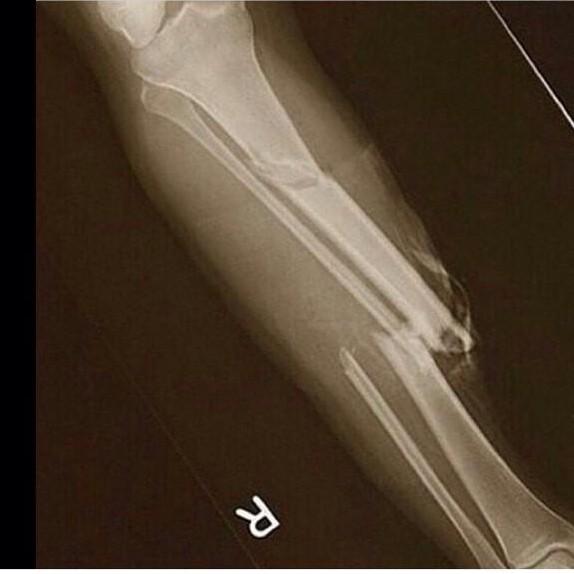

保罗-乔治右小腿X光成像.

【图】保罗乔治断腿x光图曝光 画面惨不忍睹队

【图】保罗乔治断腿图片 小腿90度折断画面惨